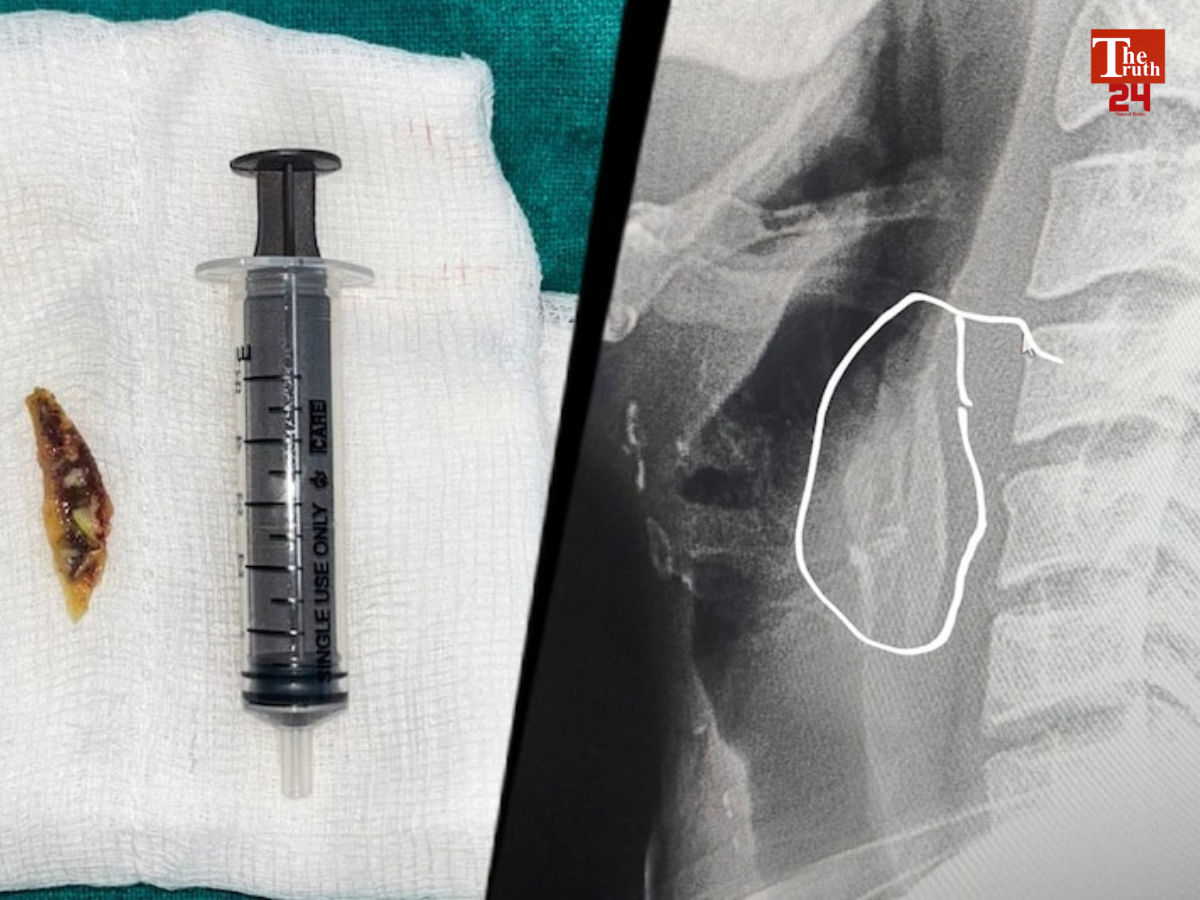

मध्य प्रदेश से एक हैरान करने वाली घटना सामने आयी है. राज्य के शाजापुर जिले में चिकन खाते समय एक 24 साल के युवक के गले में हड्डी फंस गई. जिसके बाद उसे सांस लेने में काफी दिक्कत होने लगी और उसकी हालत गंभीर हो गई. जिसके बाद युवक के परिजनों ने उसे जिला अस्पताल पहुंचाया. जहां उसे भर्ती कर लिया गया और डॉक्टर्स ने उसकी सर्जरी करके गले की हड्डी निकाली.

इस पूरे मामले को अस्पताल में तैनात EMT डॉक्टर तेजपाल सिंह जादौन ने काफी गंभीरता से लिया. जिसके बाद उन्होंने तुरंत की युवक का ऑपरेशन करने का फैसला किया. जिसके बाद में युवक का ऑपरेशन करके उसके गले से हड्डी निकाली गई. ऑपरेशन होने के बाद में अब कन्हैया लाल नाम के युवक की हालत में काफी तेजी से सुधार हुआ है और अब उसकी हालत खतरे से बाहर बताई जा रही है.